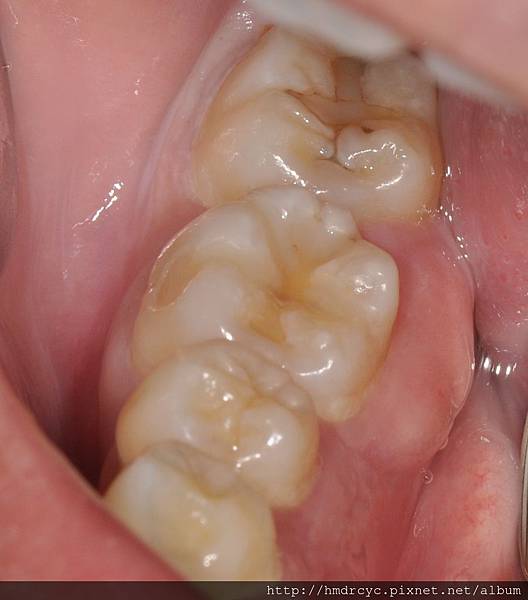

一般牙周牙肉發炎與智齒發炎

都屬於細菌多感染發炎腫脹

大多不能馬上拔除

必須先清潔吃藥等消腫才能拔